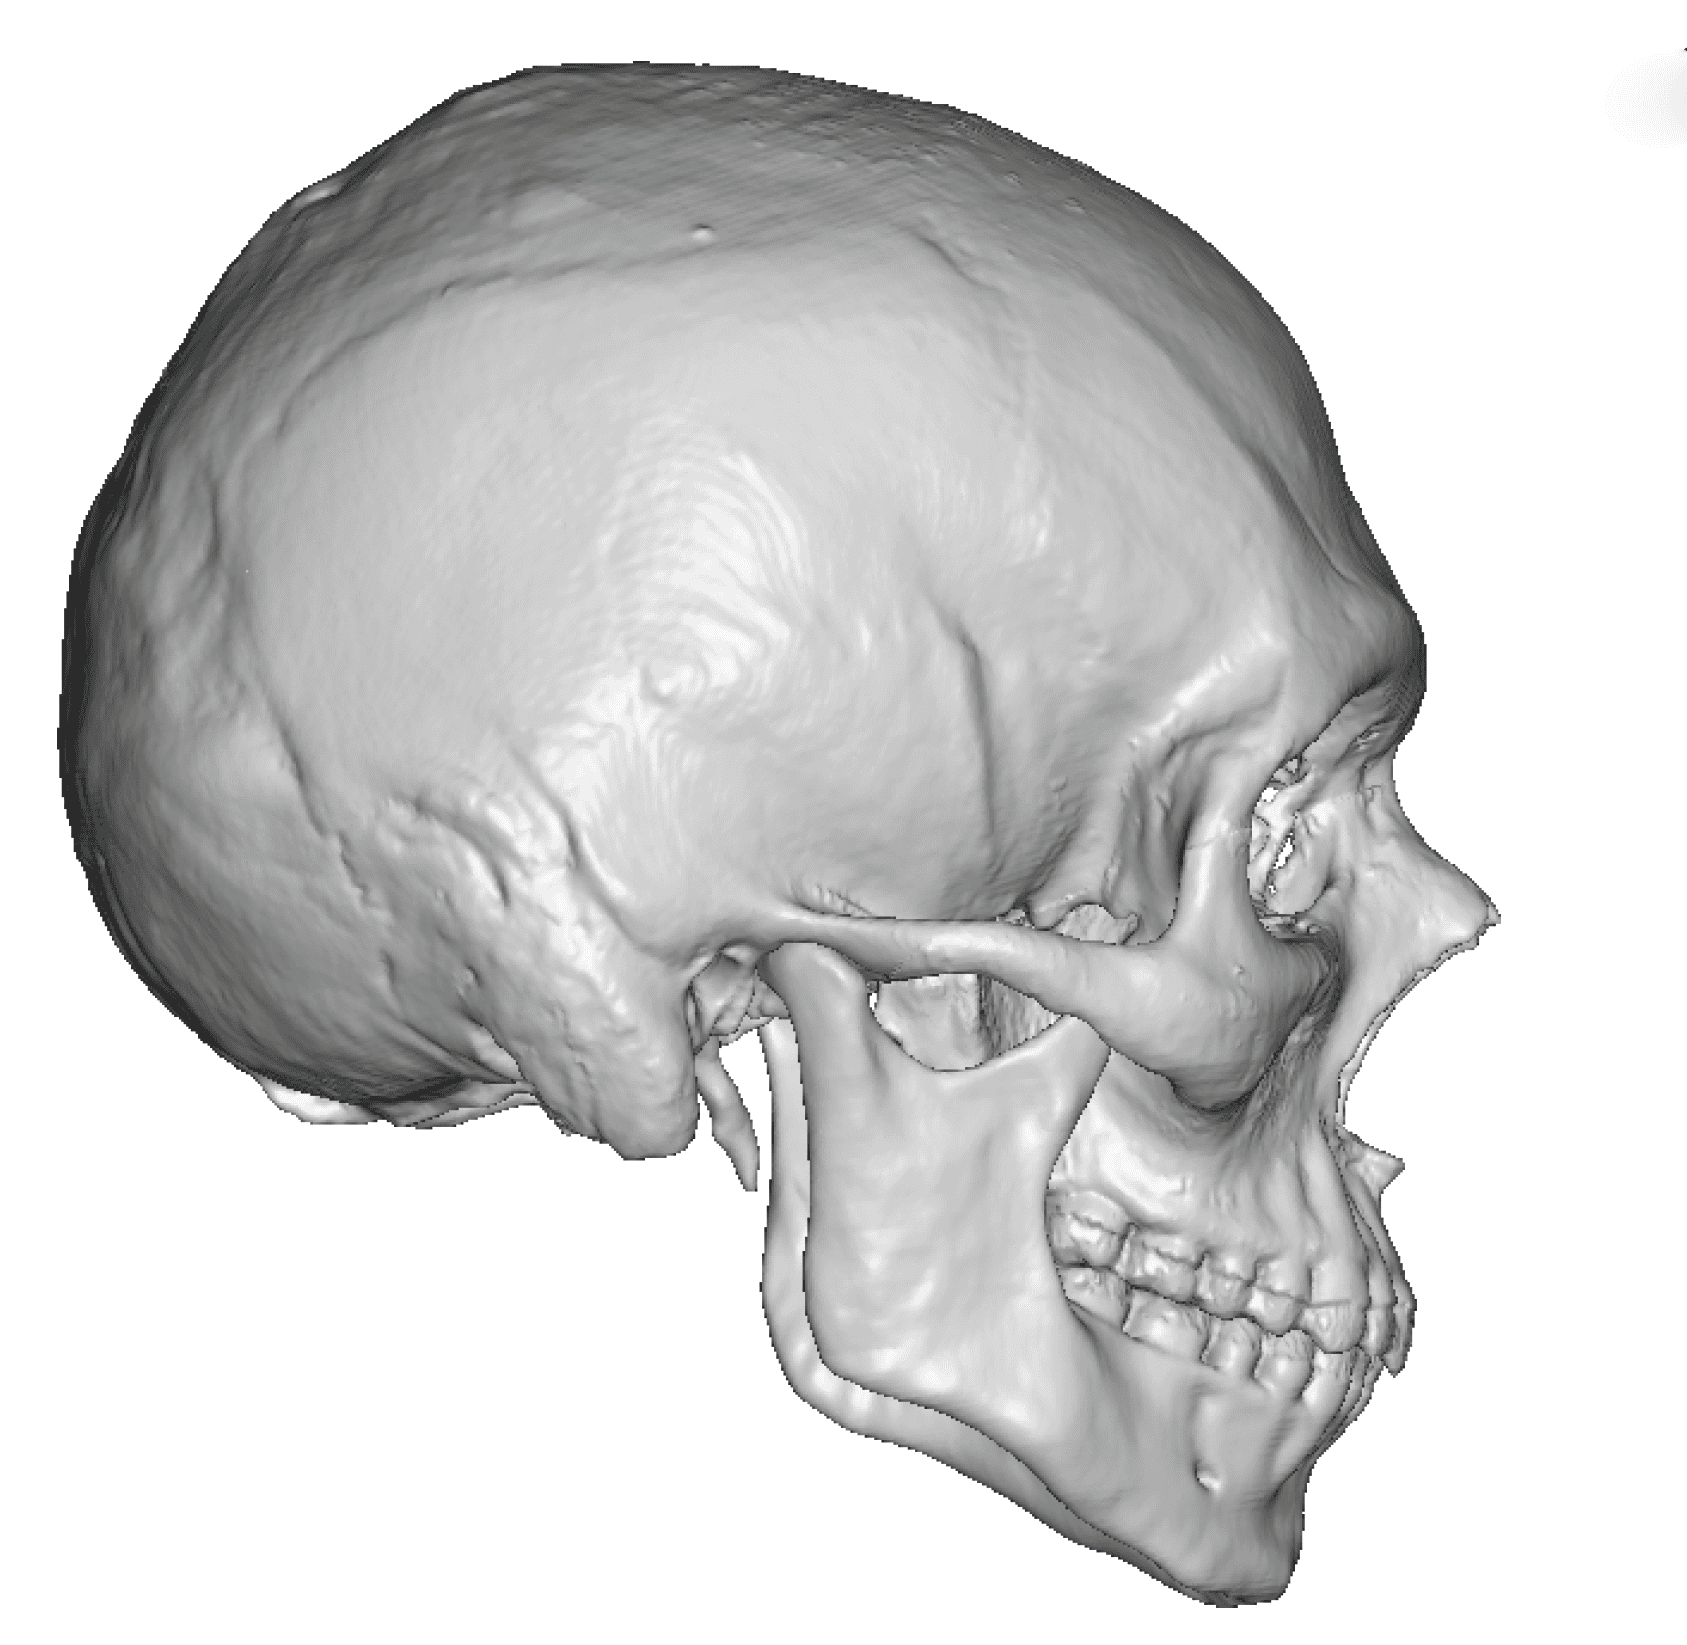

Severe narrowing skull deformity from prior sagittal craniosynostosis repair as an adult.

Complete replacement of entire skull by a custom implant with temporal fat injections.

Severe narrowing skull deformity from prior sagittal craniosynostosis repair as an adult.

Complete replacement of entire skull by a custom implant with temporal fat injections.